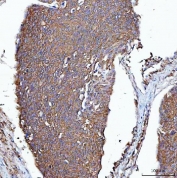

IHC staining of FFPE human esophageal squamous carcinoma tissue with PGP antibody. HIER: boil tissue sections in pH8 EDTA for 20 min and allow to cool before testing.